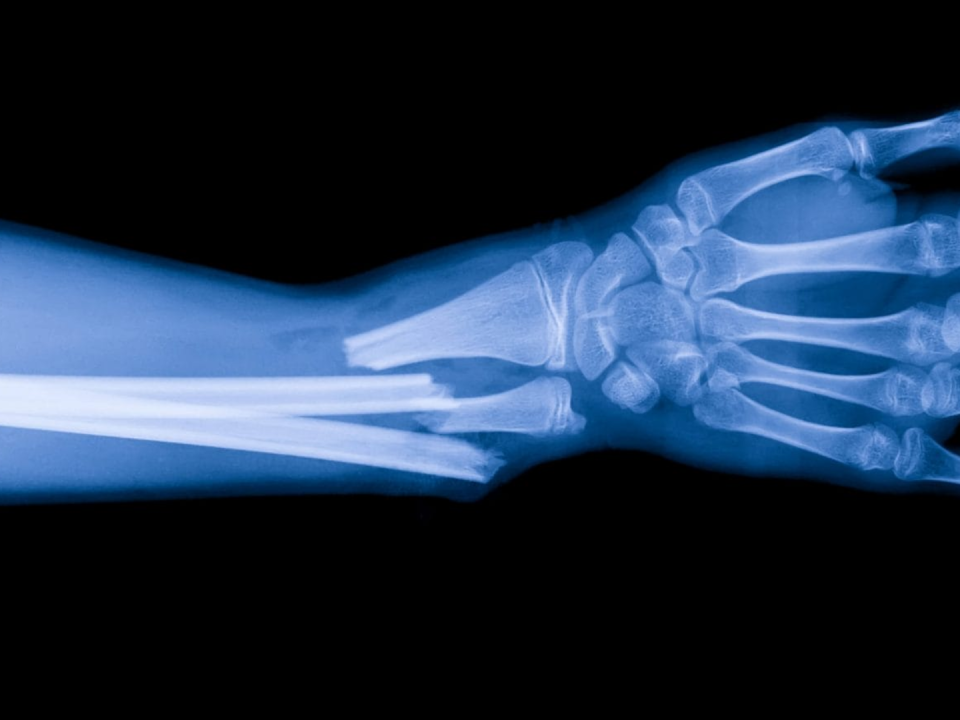

Diagnosticare deviatii axiale

Deviațiile axiale la copii – cauze, simptome și tratament

Deviațiile axiale la copii sunt o problemă comună care poate afecta sănătatea oaselor și a articulațiilor. Acestea se referă la alinierea incorectă a oaselor sau articulațiilor în raport cu axa corpului și pot cauza complicații dacă nu sunt tratate corespunzător.